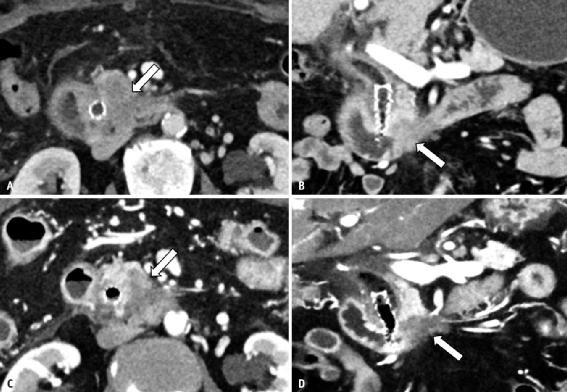

PCD-CT可实现的图像对比度优化在腹部和骨盆具有多种潜在应用,包括改善实质背景中肿瘤的可见性和轮廓,特别是所谓的“低对比度”病变,其中靶病变的CT值与解剖背景相似。例如,PCD-CT可以通过强调由于碘增强的微小差异而导致的CT值差异来增加肝脏病变(低血管和高血管肿瘤)和胰腺癌的显著性(图6)。光子计数探测器的改进的剂量效率允许在匹配的辐射剂量下使用较薄的层厚,从而降低部分容积效应(图6)。通过使用光子计数探测器单独或与VMI结合使用改进的碘对比度信号,PCD-CT图像的更高空间分辨率可以提高小病灶的可检测性,例如小的低衰减肝转移瘤(图7)或腹膜植入物(图8)。PCD的碘信号改善,可能与低能量VMI相结合,可替代地用于减少碘造影剂用量,以实现不同诊断任务的图像对比度的类似差异(图9),该方法可用于肾损伤或经历重复血管内手术的患者。

图6 67岁女性胰腺癌患者。A-D 与能量积分探测器CT(A、B)获取的轴位和冠状位2mm图像相比,PCD-CT(C、D)获取的轴位和冠状位1mm图像提供了钩状体内低密度肿瘤的更好可视化,因为PCD-CT能够突出碘对比度;同样在这些图像中,PCD-CT显示更薄层厚的能力也得到了证明,而不会显著增加图像噪声。较薄的层厚减少了小结构和病理的部分体积效应。

图7 64岁的转移性胰腺癌患者。A、B 光子计数探测器CT图像(A)显示了在随后的MRI(B)中确认的右后段(箭头)中非常小的肝转移。

图8 73岁女性,卵巢癌腹膜播散。A、能量积分探测器CT显示乙状结肠浆膜不规则,腹膜前反射有可疑结节。B、光子计数探测器CT清楚显示小肿瘤植入物导致腹膜前反射不规则和结节状增厚(箭)。